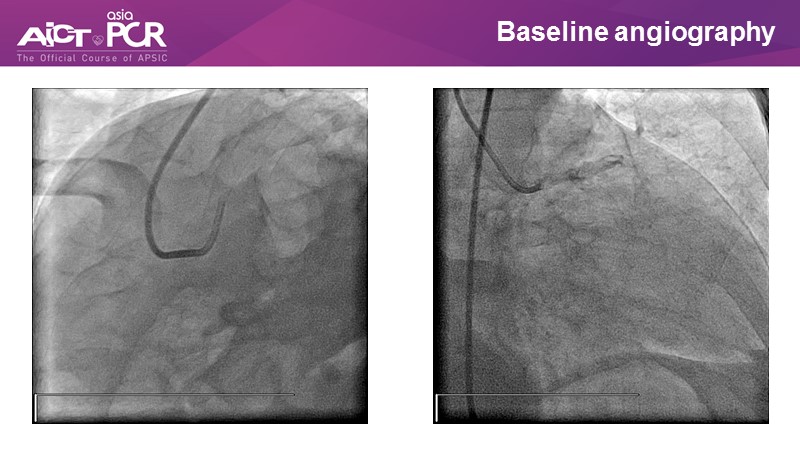

Opening - LIVE demonstration from National University Heart Centre Singapore

Chairpersons: C.K. Naber, M. A. Rosli

Panellists: K. Al Faraidy, K. T. Chan, M. C. Morice, M. Nguyen, T. Santoso, W. A. Wan Ahmad

Operators: A. Low, K. C. Y. So

Control Desk: J. Chen